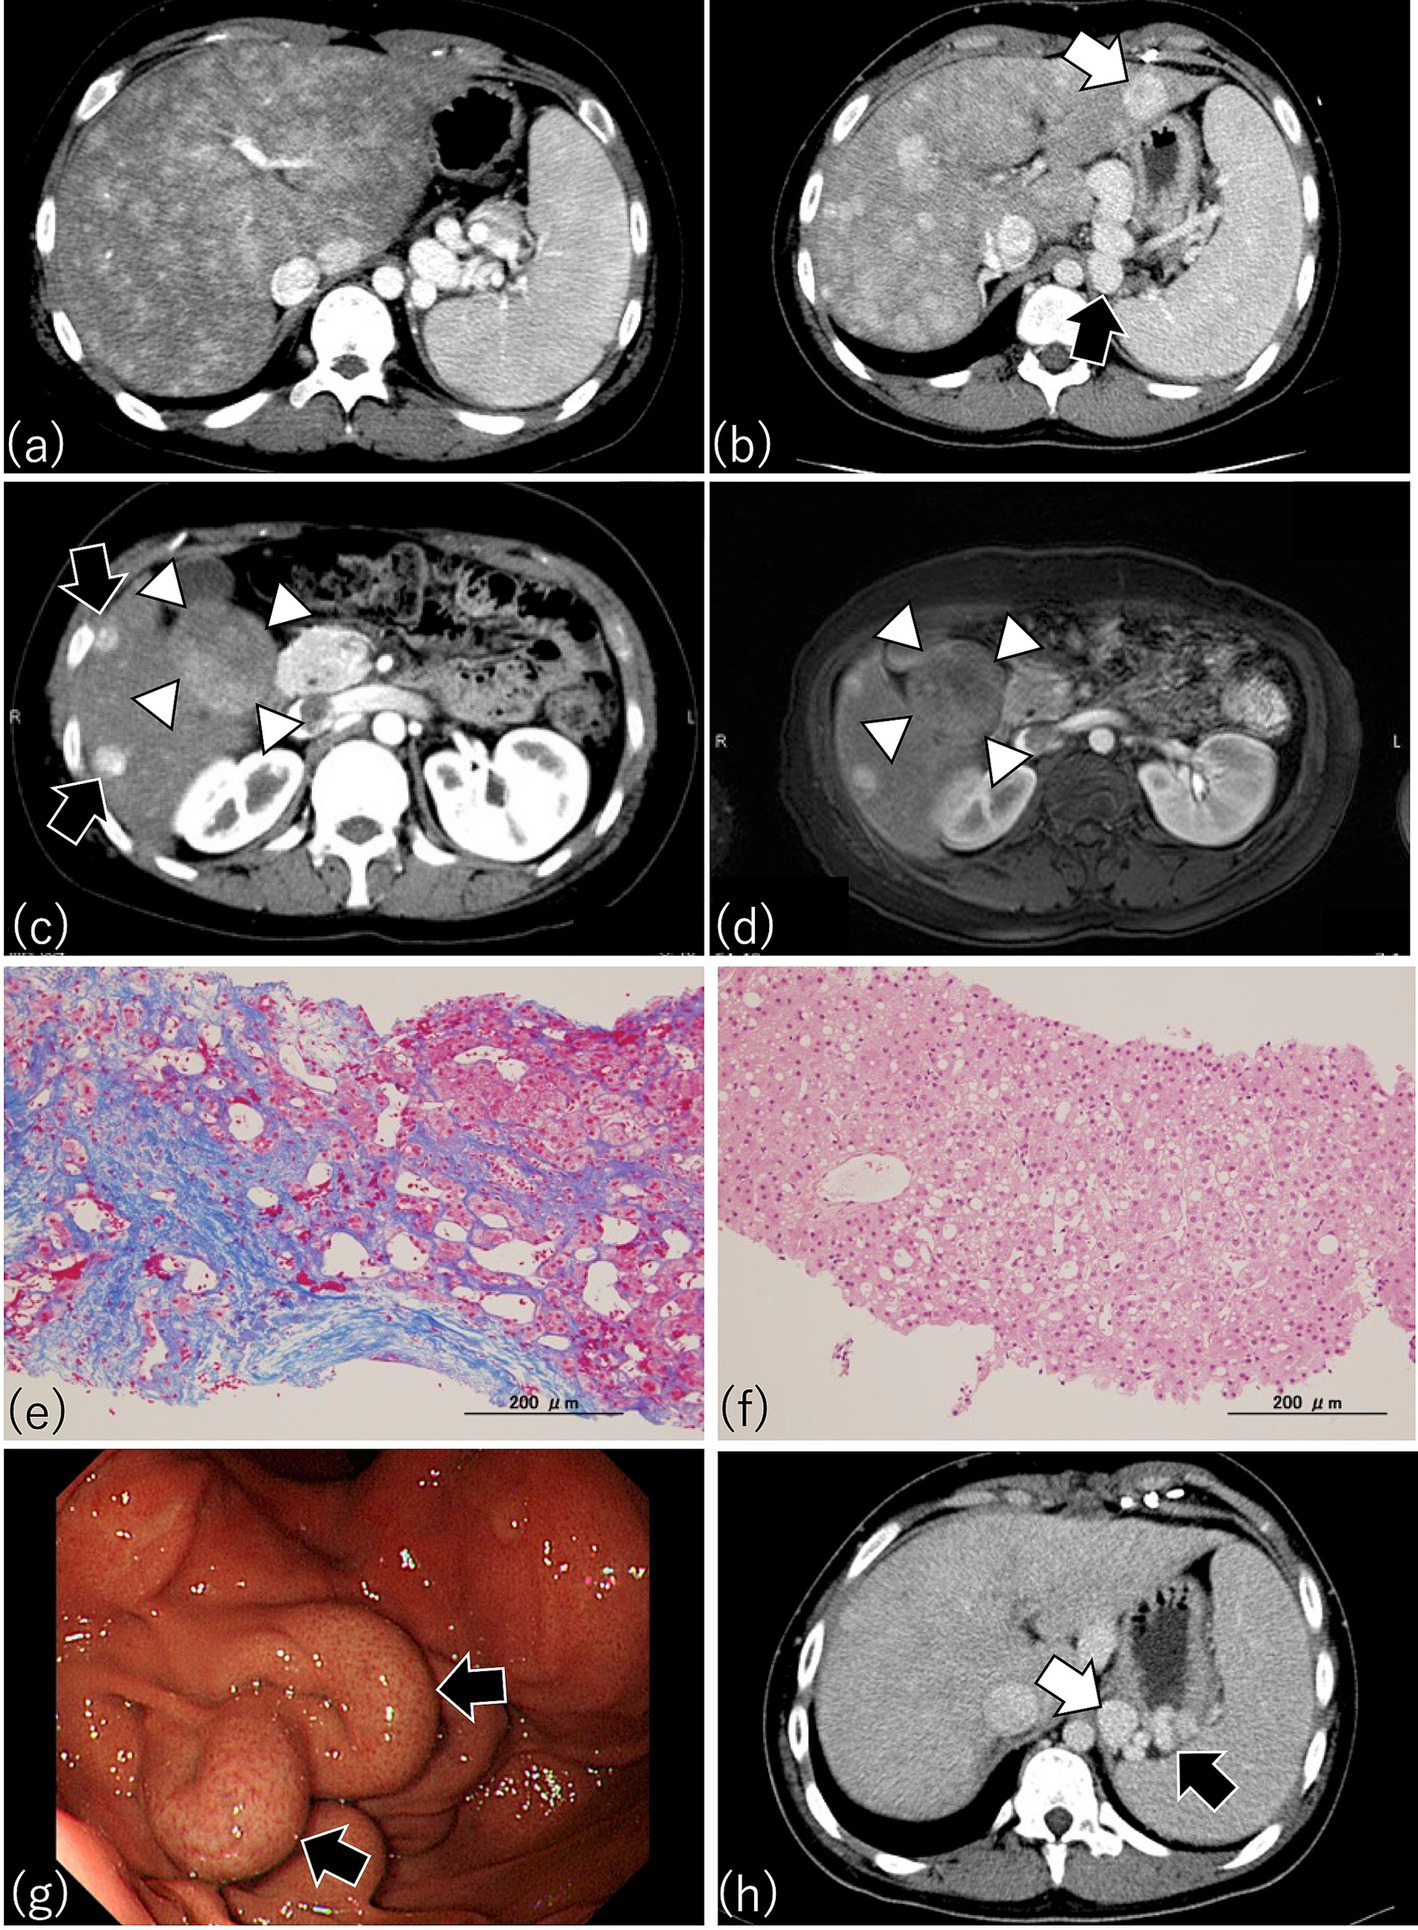

Ultrasonography, liver elastography, CT, and MRI have all been examined for their utility in post-Fontan patients (99, 100, 110–112). Frequent findings on clinical abdominal ultrasonographic images of these patients include hepatomegaly, venous dilatation (due to their elevated CVP), heterogeneous patterns in the liver parenchymal texture, nodular changes at the liver surface, and highly echoic nodules (99, 100, 110). A heterogeneous echogenic parenchymal pattern results not only from congestion but also fibrosis and fatty liver (113), such that using this parameter to estimate histologic changes in post-Fontan patients is difficult. Depending on the degree of liver congestion, veno–venous shunts between hepatic veins can be appreciated via ultrasonography. CT and MRI reveal hepatic fibrosis as heterogeneous parenchymal enhancement with a mosaic or reticular pattern (Figure 4a) (111). In addition, liver fibrosis on T2- or diffusion-weighted MRI appears as hyperintense mottled areas along the organ periphery (112). Contrast MRI scans demonstrate a reticular, patchy enhancement pattern in both the portal venous and delayed phases (114). Patients who have undergone a Fontan procedure are prone to develop a variety of benign or malignant focal liver lesions, including FNH, NRH, and HCC, all of which can be discerned or suspected by using ultrasonography, CT, or MRI (Figures 4b–f) (42, 111, 115, 116). Those imaging features are helpful in the assessment of FALD and facilitate decision-making regarding further examination (e.g., liver biopsy) and treatment strategies. Therefore, collaboration with imaging and interventional radiologists and hepatologists familiar with the unique imaging features of FALD is key.

Figure 4

Characteristic findings by CT, MRI, and endoscopy in patients after Fontan procedure. (a) This patient underwent Fontan surgery 17.5 years earlier. Arterial phase imaging of dynamic CT shows diffusely heterogeneous enhancement of the liver, with pronounced peripheral reticular decreased signal caused by venous congestion. The spleen is enlarged, indicating portal hypertension. (b) A patient who had the Fontan procedure 14 years earlier. Dynamic CT shows an enlarged liver with a heterogenous texture and a lesion consistent with focal nodular hyperplasia (FNH) (white arrow). A gastro-renal shunt (black arrow) and enlarged spleen, indicating portal hypertension, are present also. (c) This patient received the Fontan procedure 16.8 years earlier. Arterial phase imaging of dynamic CT shows FNH-like hypervascular lesions (black arrows) and a focal liver lesion (diameter, 5 cm) with a mosaic pattern in S5 and S6 (white arrowheads) (d) Contrast-enhanced MRI with gadolinium ethoxybenzyl diethlenetriamine pentaacetic acid (Gd-EOB-DTPA) of the same patient as in (c) because the mosaic pattern in S5 and S6 suggested hepatocellular carcinoma (HCC). As shown through dynamic CT (c), contrast-enhanced MRI also revealed a mosaic pattern (white arrowheads) suggestive of HCC in the focal liver lesion in S5 and S6; therefore, a targeted liver biopsy was obtained. (e) Azan staining of the biopsy from the liver parenchyma of (c) revealed dilated sinusoids and extensive sinusoidal fibrosis with bridging fibrosis, thus corresponding to a congestive hepatic fibrosis score (CHFS) of 3. (f) H&E staining of the biopsy from the focal liver lesion with the mosaic pattern in (c) disclosed not HCC but regenerative nodular hyperplasia. (g) Esophagogastroscopy in this patient who underwent the Fontan procedure 14 years earlier disclosed an enlarged nodular gastric varix (Lg-cf, F2, CW, RC0), thus indicating the need for prophylactic therapy for risk of bleeding. (h) Portal phase imaging with dynamic CT in the same patient as in (g) reveals a gastric varix (black arrow) associated with a gastro-renal shunt (white arrow). The presence of the gastro-renal shunt indicates that balloon-occluded retrograde transvenous obliteration is available as a treatment option for the gastric varix in this patient.

Because the risk of developing HCC increases rapidly after 10 years postoperatively, imaging modalities including ultrasonography, contrast CT, and MRI are necessary during the long-term follow-up of post-Fontan patients so that HCC will not be missed. However, options regarding imaging modality available for patients with pacemakers are limited. To further assess whether focal liver lesions are HCC, contrast-enhanced MRI using gadolinium ethoxybenzyl diethlenetriamine pentaacetic acid (Gd-EOB-DTPA) or contrast-enhanced ultrasonography with sonazoid are valuable (131–133). The time course of the Gd-EOB-DTPA-enhanced MRI signal intensity in HCC of FALD differs from that of FNH in FALD and of HCC in chronic hepatitis C (131). In contrast-enhanced ultrasonography, poorly differentiated HCC of FALD shows homogeneous enhancement during the arterial-dominant phase and progressive hypoechogenicity relative to the adjacent liver parenchyma during the portal-dominant phase; in contrast, a regenerative nodule is an isoechoic mass relative to the adjacent liver parenchyma during the portal-dominant phase (133). However, despite the use of Gd-EOB-DTPA-enhanced MRI, differentiating HCC from FNH or NRH in the livers of post-Fontan patients can remain difficult (Figures 4c,d) (111). In these cases, ultrasound-guided percutaneous targeted biopsy of a focal liver lesion may be necessary to exclude the possibility of HCC (Figures 4c–f). Because the diagnosis of HCC in post-Fontan patients requires careful interpretation of several imaging modalities and (sometimes) histologic confirmation, appropriate assessment of focal liver lesions in this population requires collaboration among radiologists, hepatologists, and histopathologists.